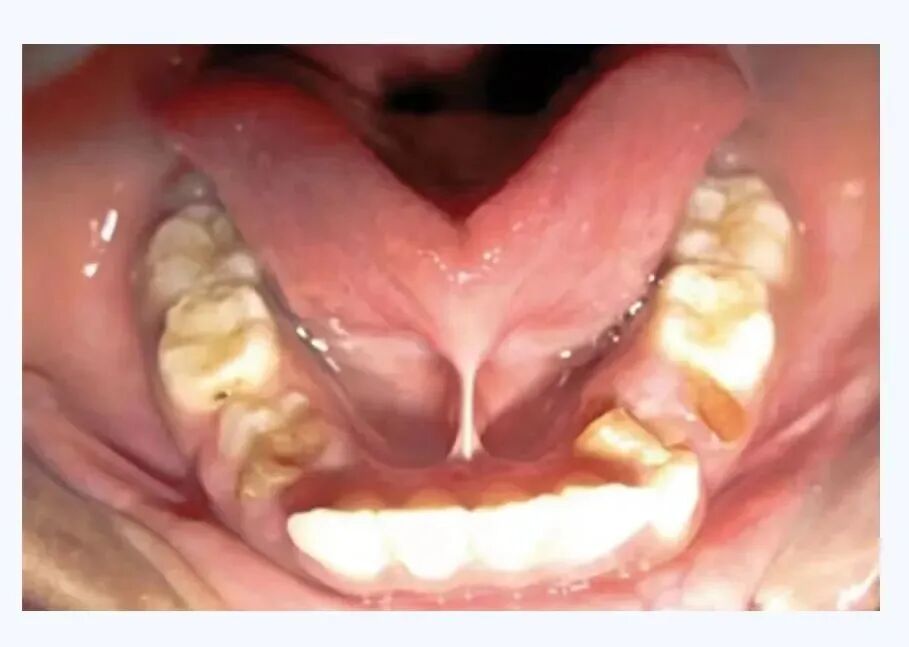

舌系带是舌头正下方那个细长的粘膜组织,翘起舌头时可以见到,用老百姓通俗的话讲,就是舌筋。

舌系带过短是先天发育性疾病,属于发育性异常,是舌系带附着于舌腹部近舌尖处,导致伸舌受限。

导致舌不能自由前伸并且舌尖上抬比较困难,如前伸舌时舌尖呈“W”型(正常人前伸时舌尖呈“V”型)